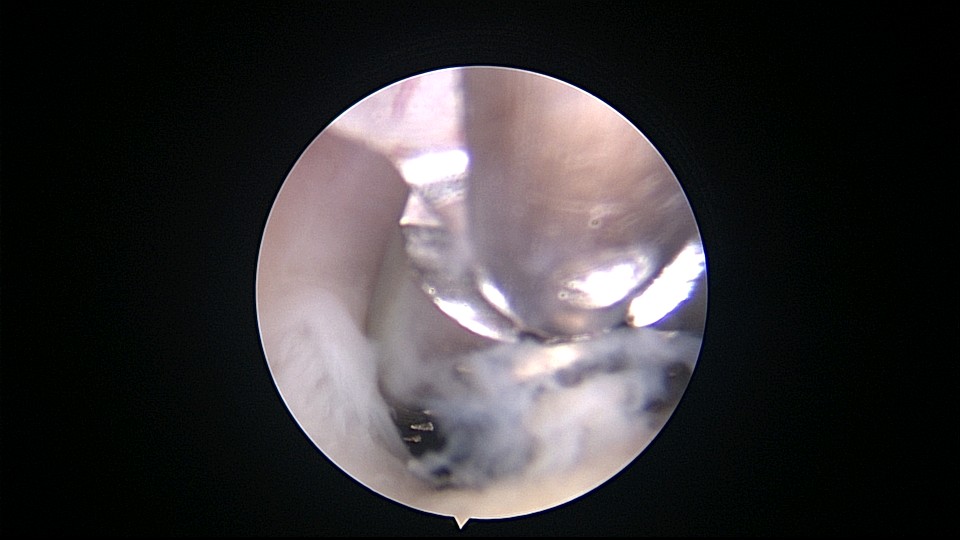

患者56岁,G2P1,剖宫产1次。安环30年,绝经7年,外院取环失败,形成假道。子宫后倾后屈位,宫颈外口萎缩狭小,宫颈管扩张膨大,宫颈管左前壁假道,宫颈内口狭窄坚硬,宫腔镜见宫腔偏向右后方,并向左后侧屈,镜子艰难进入宫腔,O型环位置正常,异物钳取出,宫腔无其他异常。